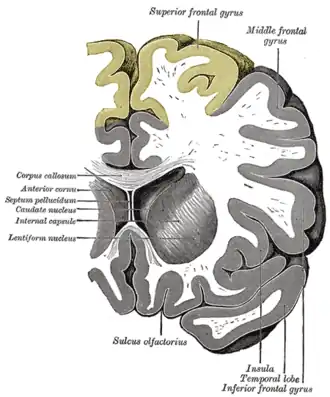

Coronal section through anterior cornua of lateral ventricles. Superior frontal gyrus is shown as yellow. | |

| Part of | Frontal lobe |

| Artery | Anterior cerebral |